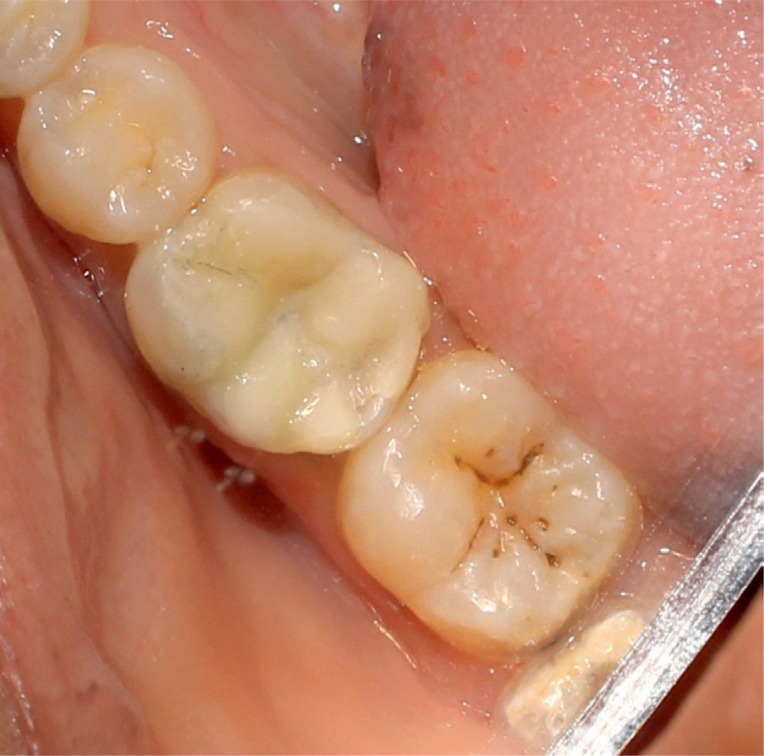

Figure 13Clinical view after one year.